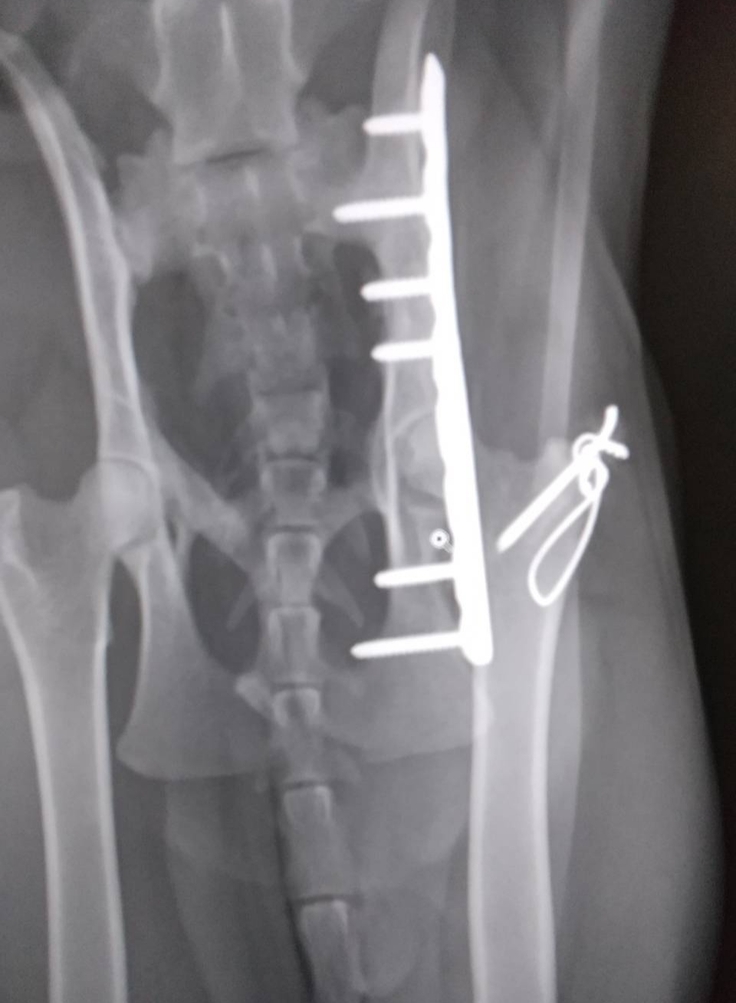

三毛猫ちゃんのレントゲンです

↑現在

完治告知いただきました😣✨